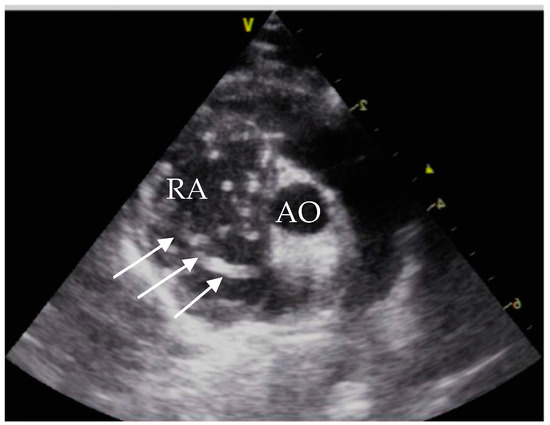

Echocardiographic exams were performed by a single experienced operator with GE vivid™ S6, equipped with a microconvex GE 7s probe. The right atrium showed severe dilatation, and several double lined hyperechoic echoes close the tricuspid valve were seen (Figure 2). The suspected diagnosis based on the echocardiographic findings and the clinical signs was an infection with D. immitis.

At initial presentation, the cat showed dyspnoea, ascites and double hyperechoic parallel lines in the echocardiography, which is the typical presentation for D. immitis in echocardiography [26]. The sensitivity of echocardiography for detection of D. immitis is operator-dependent and is reported between 88% and 100%. False positive results can be caused by right ventricular chordae tendineae [27].

Figure 2. Echocardiography showing heartworms, right parasternal short axis view. RA = right atrium; AO = aorta; white arrows = heartworms.